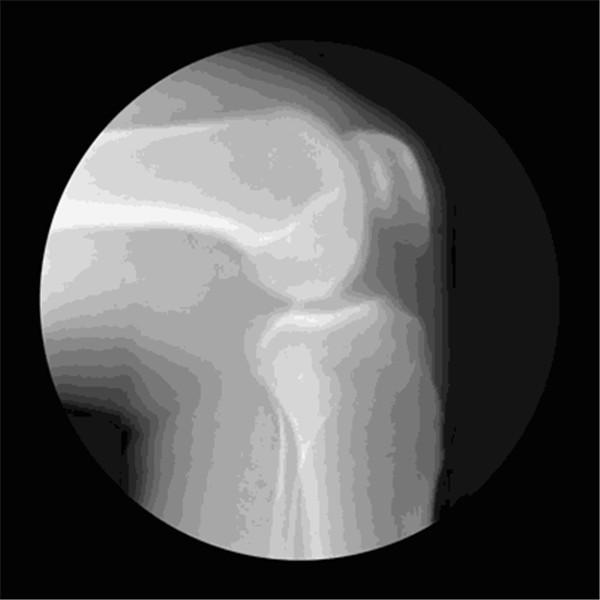

关节是骨骼之间的连接点,一旦关节出了问题,人的行动力就会受限,久之人就垮了。

关节不好的患者,对心血管系统、呼吸系统、骨骼肌系统等会造成一定影响。因关节病长期卧床的老年人,也会引发骨质疏松、褥疮、消化系统疾病。

关节在生活中最怕几个字

1、怕老

随着年龄的增长,人体软骨营养缺乏,骨骼中的无机物增多,骨骼弹力与韧性减低,易导致关节软骨退行性病变。

2、怕胖

体重增加,下肢关节承重的压力也会增加,引起体位、步态变化,改变关节的生物力学,发生膝内翻或膝外翻,也就是常说的“O”形腿或“X”形腿。

3、怕伤

在运动、出行的过程中,如果出现急性外伤,一定要及时去医院治疗,以免留下后遗症。

不及时治疗或充分休息,容易留下病根,比如“习惯性崴脚”。

4、怕勤

关节用得太狠,容易导致机械磨损,破坏软骨。

频繁爬山、爬楼等是非常伤害关节的。建议大家平时通过慢跑、游泳锻炼,既不损伤关节又能锻炼。

5、怕冷

关节受凉会引起疼痛,易导致关节僵硬。